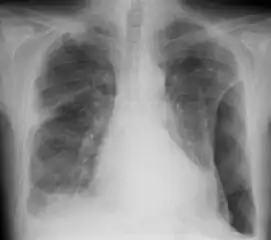

![]() | |

| Fibrothorax as seen on the left side of a chest x-ray (person's right side) | |

A fibrothorax can typically be diagnosed by taking an appropriate medical history in combination with the use of appropriate imaging techniques such as a plain chest X-ray or CT scan.[1] These imaging techniques can detect fibrothorax and pleural thickening that surround the lungs.[11] The presence of a thickened peel with or without calcification are common features of fibrothorax when imaged.[1] CT scans can more readily differentiate whether pleural thickening is due to extra fat deposition or true pleural thickening than X-rays.[1]

If a fibrothorax is severe, the thickening may restrict the lung on the affected side causing a loss of lung volume.[11] Additionally, the mediastinum may be physically shifted toward the affected side.[1] A reduction in the size of one side of the chest (hemithorax) on an X-ray or CT scan of the chest suggests chronic scarring.[9] Signs of the underlying disease causing the fibrothorax are also occasionally seen on the X-ray.[9] A CT scan may show features similar to those seen on a plain X-ray.[11] Lung function testing typically demonstrates findings consistent with restrictive lung disease.[9]